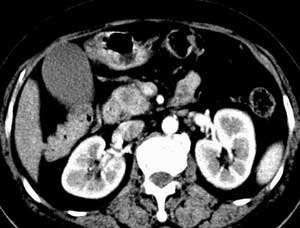

我去会诊,看他的腹部CT片。胰腺上有一个包块,看片子应该是胰腺癌,多发肝脏转移,肝内胆管扩张。我看着那张冷酷无情的片子,由不得叹了口气。我知道这样的一张片子意味的大概就是四个月的生存期。然后跟病人家属交待病情,没有手术机会,预后差,生存期短,进展快。我无数次的交待过病情,我知道我有着职业的沉着和冷静。家属按照惯例被我交待哭了。我交待哭过许多人。突然的这种对自家亲人的无情的宣判其实谁都接受不了。从老伴儿到大儿子到二儿子纷纷跟我表达的是无法接受,不可思议。看着还好好的一个人怎么就会被宣判了不到半年的有期徒刑呢。